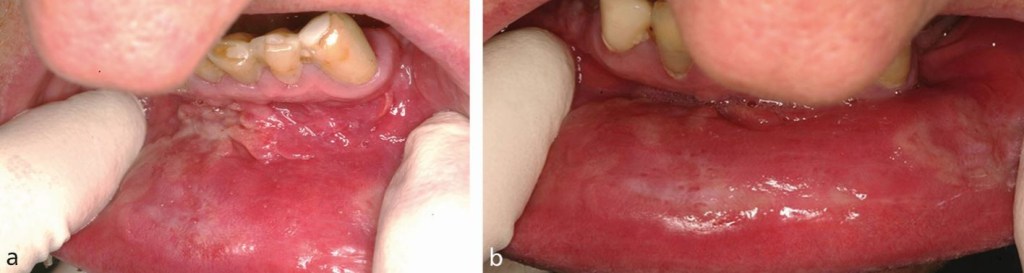

Na cavidade oral, surgem placas mucosas — lesões esbranquiçadas ou acinzentadas, bem delimitadas, levemente elevadas e de superfície úmida.

Podem ser múltiplas e simétricas, acompanhadas de lesões cutâneas em tronco, palmas das mãos e plantas dos pés.